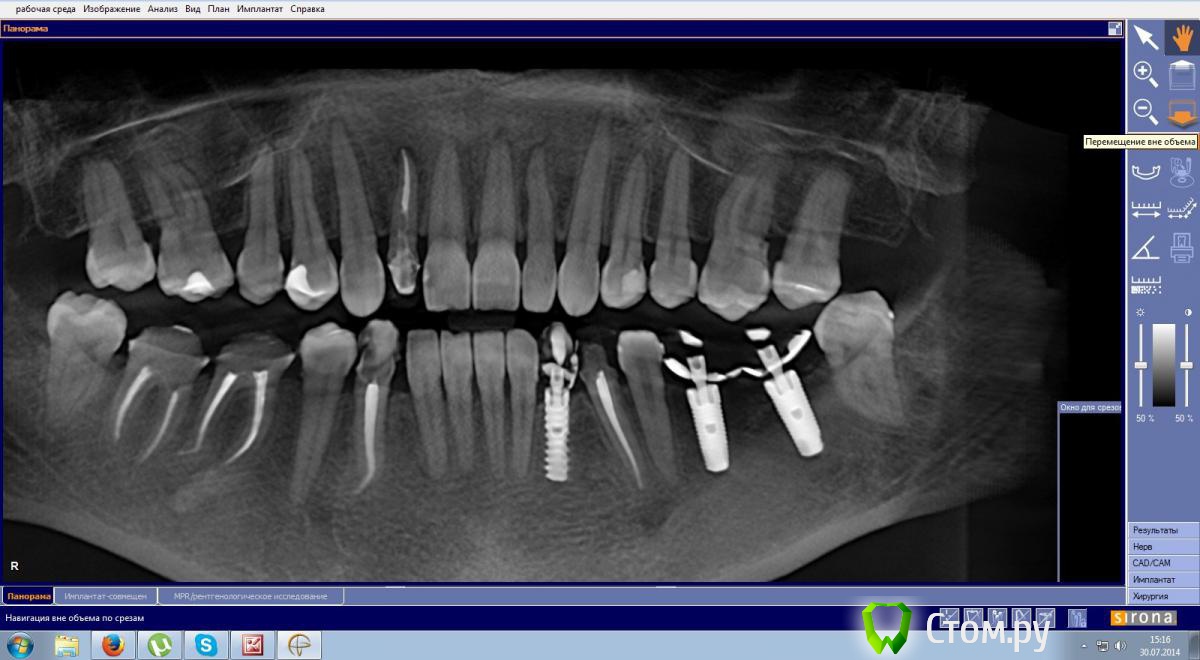

Эндж Опубликовано 1 августа, 2014 Поделиться Опубликовано 1 августа, 2014 Здравствуйте! Мне поставили временные коронки на импланты 6 и 7 слева и на свои 6 и 7 справа. Коронки сдвоенные, что стало для меня неприятным открытием. Я попросила постоянные разделить, врач ответил, что на своих можно будет поставить отдельные, а на импланты нет, потому что так будет лучше функционально. Хотелось бы услышать ваши мнения, на самом деле это так, или мне стоит настоять на своем? Ссылка на комментарий